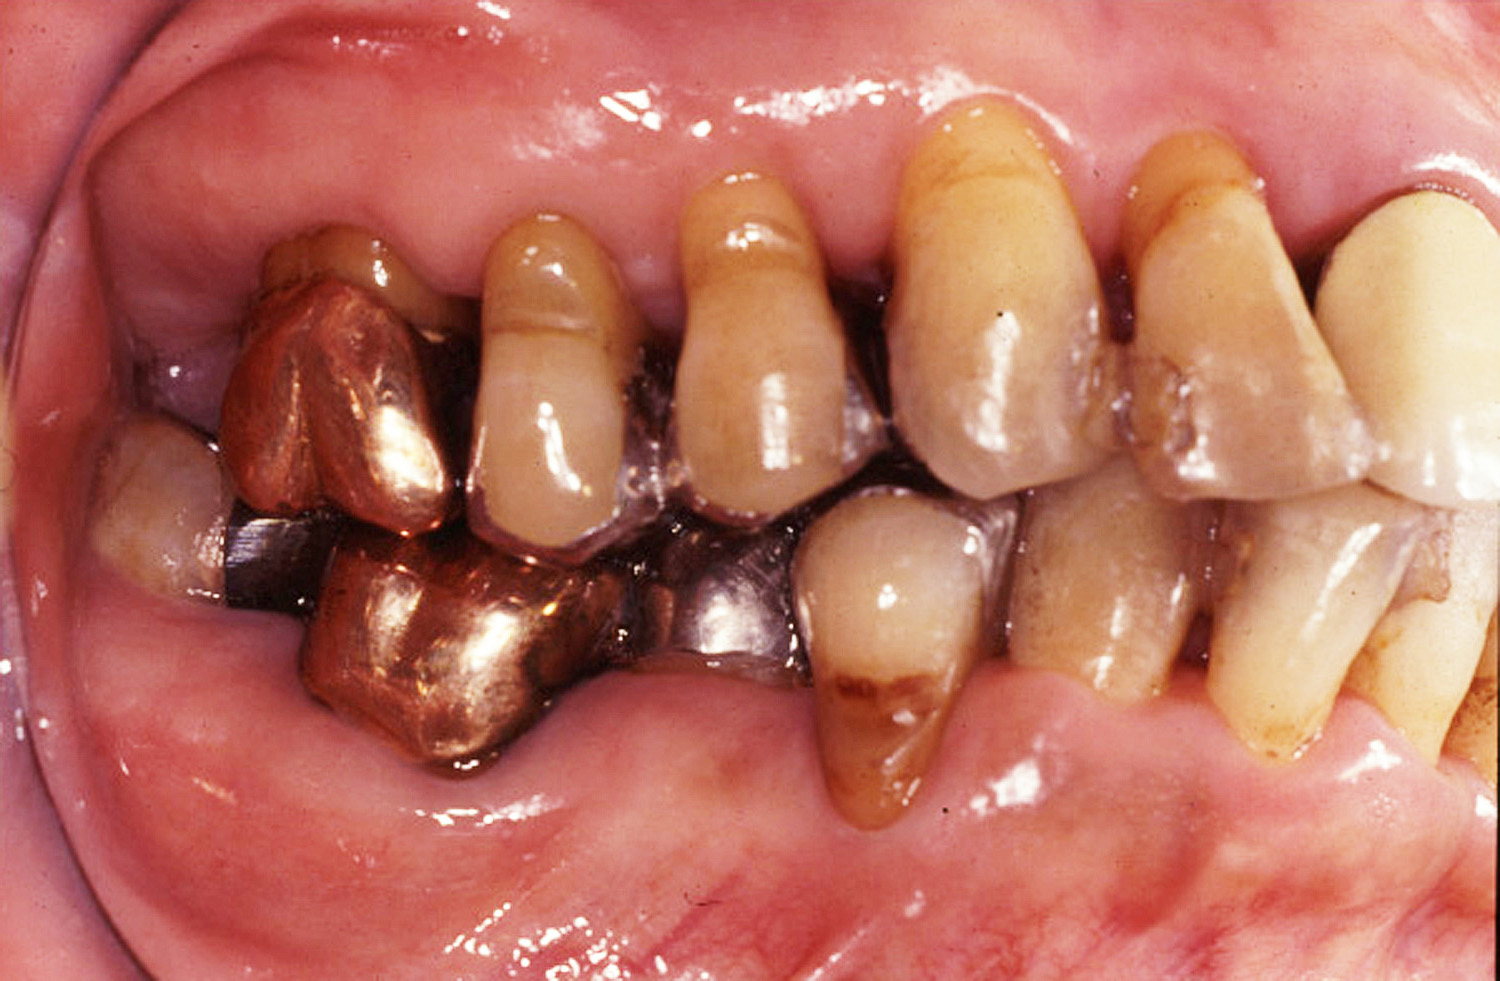

歯周治療症例3

本症例は50才代後半の女性で、全顎的なインプラント治療を希望して来院。

精査した結果、全顎的に中等度から重度の歯周炎が認められたものの、抜歯に至る歯はなかったため、通常の歯周治療(歯周外科を含む)を立案。

全顎的な歯周治療に伴い、補綴、う蝕、歯内処置を行った。臼歯部は全て外科処置を行っている。

術後は3年目の写真であるが、歯周組織の状態は安定している。